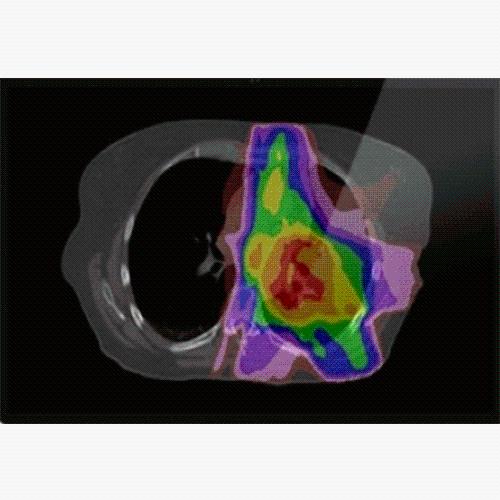

Supporting image modalities such as CT, multi-sequence MR, PET and SPECT

Rigid and modality-specific deformable image registration (DIR)

Adaptive recontouring, dose warping and summation

ALIGN ANATOMICAL, FUNCTIONAL AND 4D IMAGING